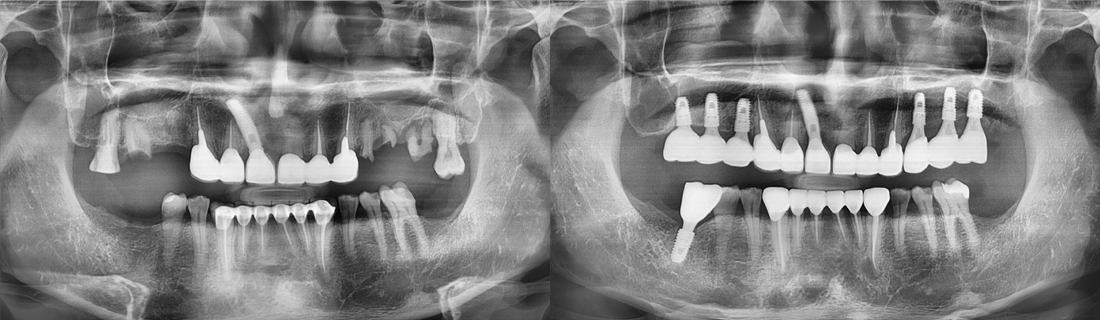

백년치과를 만나기 전과 후

나의 치아 사례와 비슷한 환자분들이 치료 후 어떻게 변화되었는지 직접 확인해보세요.

백년치과 임플란트를 만나기 전과 후